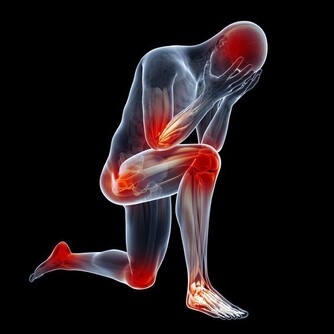

線索六:內八字

預警:風濕性關節炎

這種炎症會造成內八字的步態,有85%的風濕性關節炎患者會表現出這種特徵。它在醫學上被稱為膝外翻或者外翻足,表現為小腿無法伸直,向外側彎曲。這種步態非常與眾不同,看上去笨拙,雙膝併攏在一起,而踝關節外翻。